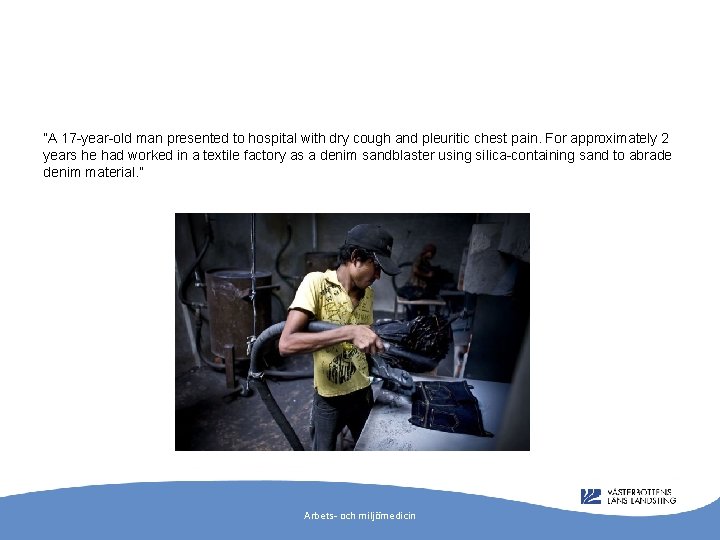

”A 17 -year-old man presented to hospital with dry cough and pleuritic chest pain. For approximately 2 years he had worked in a textile factory as a denim sandblaster using silica-containing sand to abrade denim material. ” Arbets- och miljömedicin